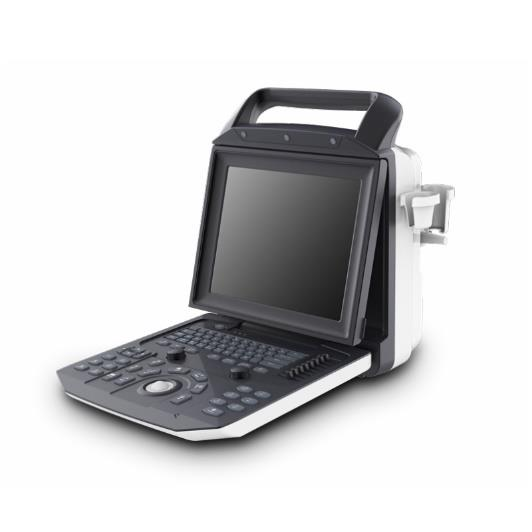

PORTABLE ULTRASOUND SYSTEM

PORTABLE ULTRASOUND SYSTEM

ULTRASOUND MACHINE I50 - ZONCARE BLACK AND WHITE

ULTRASOUND MACHINE I50 - ZONCARE BLACK AND WHITE

MINDRAY DC 80 X INSIGHT ULTRASOUND

MINDRAY DC 80 X INSIGHT ULTRASOUND